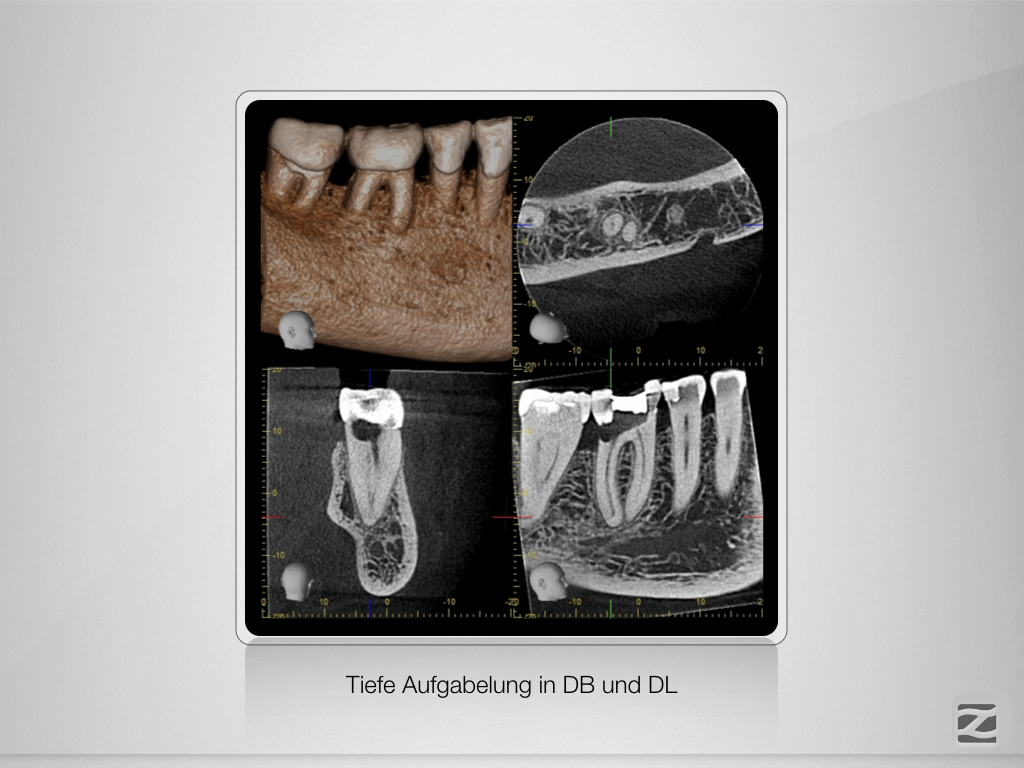

46D.006

Tiefe Gabelung mit 90 Grad nach distal